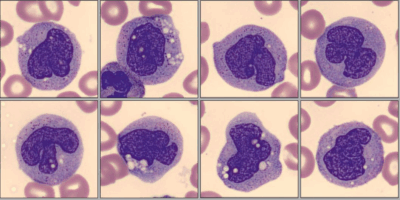

Paciente de 2 anos, sexo feminino, foi levada ao pediatra por seus pais devido a febre, fadiga, fraqueza, perda de peso e falta de ar. Eles também notaram pequenas manchas vermelhas na pele e hematomas com facilidade. O pediatra solicitou um hemograma completo. A análise do esfregaço foi realizada no CellaVision® DM-9600:

No software CellaVision® Remote Review, o analista de plantão pôde observar neutropenia com granulação tóxica, alguns linfócitos grandes granulares (LGLs), monócitos com aparência imatura e um número elevado de eritroblastos (NRBC) em diferentes estágios de maturação e com características displásicas. Ela também pôde observar um grande número de células imaturas grandes, com núcleos semelhantes aos de blastos, apresentando um ou mais nucléolos, citoplasma basofílico abundante com grânulos azurófilos finamente distribuídos e vacuolização. Algumas dessas células imaturas apresentavam núcleos dobrados e convolutos, com uma estrutura de cromatina delicada em forma de renda, e citoplasma azul acinzentado com grânulos azurófilos e vacúolos.